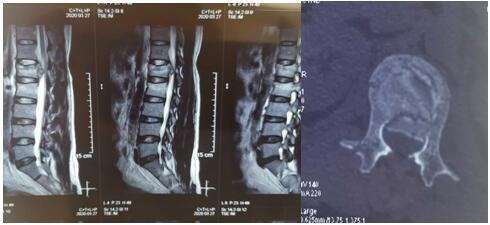

2020年3月26日夜,我院骨科二病區(qū)收住1例高處墜落傷致腰椎爆裂性骨折伴脊髓圓錐損傷、骨盆骨折、失血性休克合并右下肢深靜脈血栓形成患者,曹某,男性,42歲。查體:腰段及骨盆處壓痛,骨盆分離與擠壓試驗陽性,鞍區(qū)感覺減退。急診行MRI示:腰1椎體爆裂性骨折、腰2椎體壓縮性骨折,脊髓損傷;X線、CT+三維重建示:復(fù)雜骨盆骨折。患者系全身多處、多發(fā)復(fù)雜骨折,病情危重,手術(shù)風(fēng)險及難度高??浦魅瓮鹾捷x博士組織科室骨干醫(yī)生與神經(jīng)介入科醫(yī)生,經(jīng)深入討論后制定了詳細、縝密、有序的綜合救治方案,征得家屬同意后,急診在局麻下行下腔靜脈濾網(wǎng)植入術(shù),植入順利,遂急診在全麻下行腰1爆裂性骨折并脊髓圓錐損傷、腰2椎體壓縮性骨折切開復(fù)位、椎板切開減壓椎弓根螺釘內(nèi)固定術(shù),待病情穩(wěn)定后再二期行骨盆骨折切開復(fù)位內(nèi)固定術(shù)。

術(shù)前影像學(xué)資料如下: